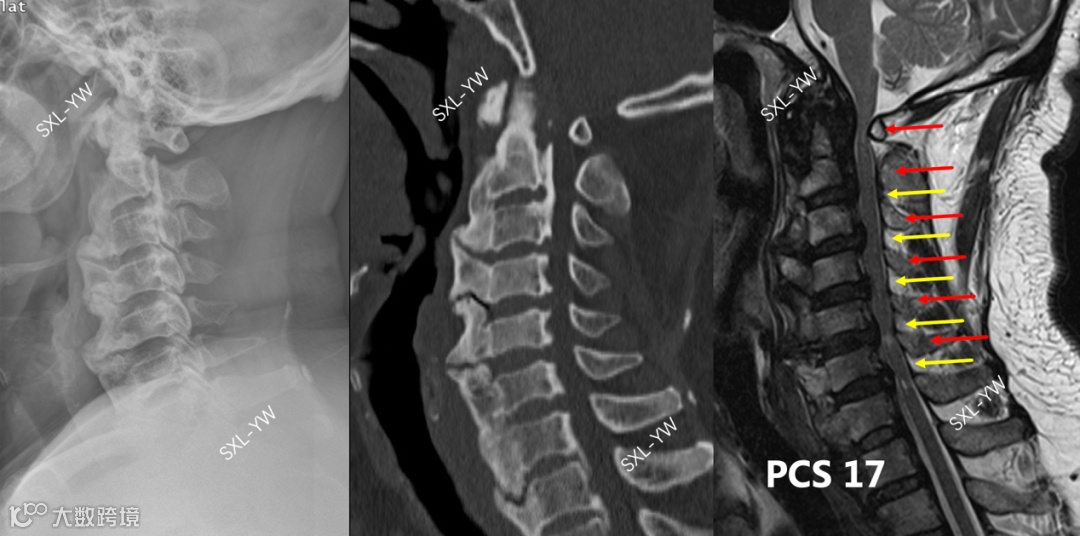

图8 该OPLL患者超出K线使用范畴,骨化累及上颈椎、合并小寰椎畸形,手术减压范围超过C2-7节段,不能用K线做术前指导。该患者PCS评分高达17分,单开门术后神经功能改善的可能性很大